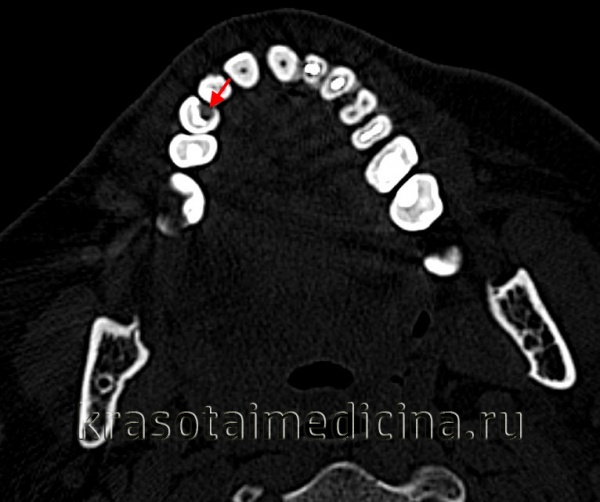

Диагностика

Диагностируют кариес во время визуального и инструментального осмотров стоматолога. Субъективные ощущения пациента позволяют судить о глубине процесса, но не являются основными диагностическими критериями. В процессе диагностики проводится прицельная рентгенография зуба, электроодонтометрия.

- Рентгенологическое исследование. Пациенту выполняется внутриротовой прицельный снимок одного или двух-трех больных зубов. На нем хорошо визуализируются размеры и глубина очага, что позволяет оценить целостность границы между дентином и цементом. Особое внимание уделяется расстоянию от дна кариозной полости до пульпарной камеры.

Проведение термодиагностики позволяет выявить кратковременную болевую реакцию на горячее и холодное, быстро проходящую после прекращения действия раздражителя. Электроодонтодиагностика при глубоком кариесе выявляет реакцию пульпы на ток силой 2-6 мкА; иногда отмечается снижение возбудимости пульпы до 10-12 мкА. При подозрении на вторичный глубокий кариес, развившийся под пломбой, дополнительно выполняется рентгенография или радиовизиография.